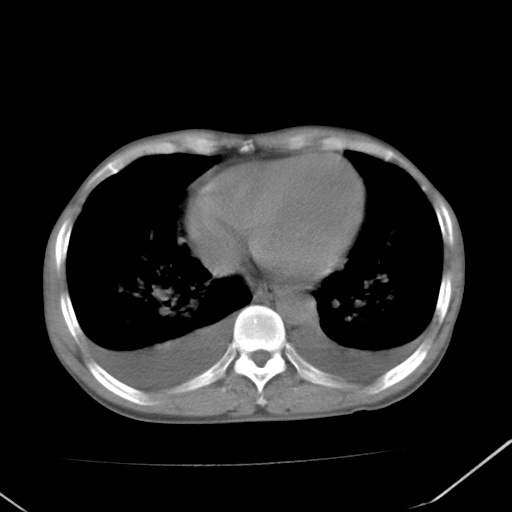

男、42岁、咯血3天。既往有甲亢、贫血、血尿蛋白尿史多年。血象:wbc:6.   中性粒:70.6%。

左心房增大,考虑心衰,肺水肿。

心影增大密度略低,双肺磨玻璃样高密度影及双侧胸腔积液,考虑心功能不全继发双肺肺水肿及双侧胸腔积液。心影密度略低,考虑贫血所致。